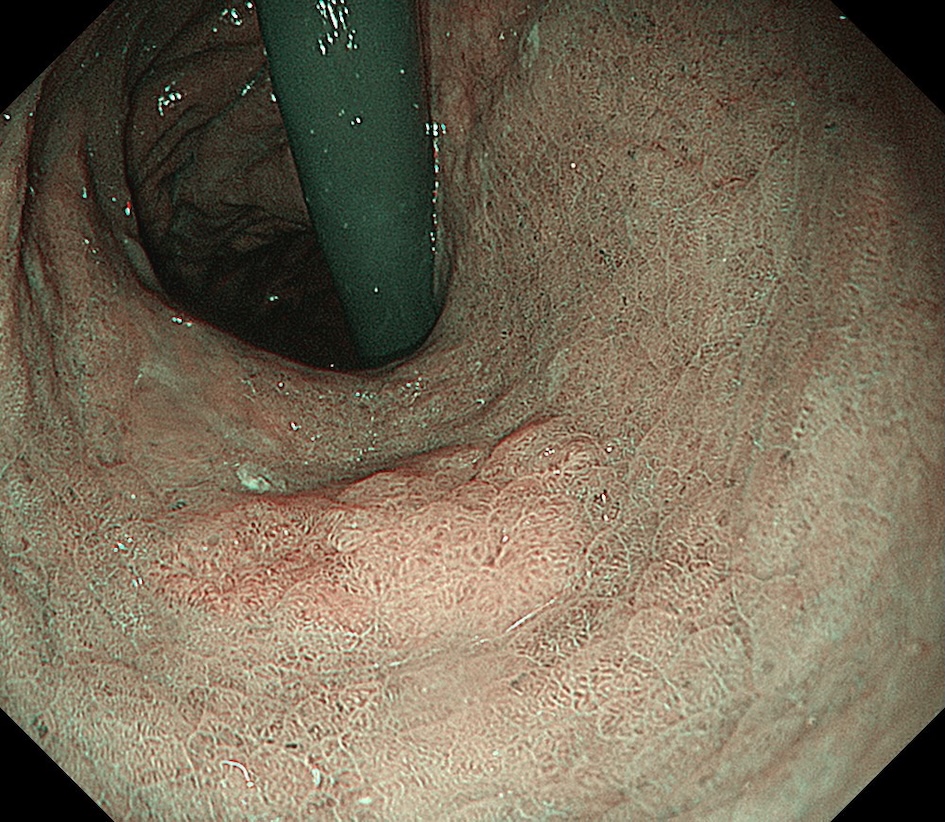

• NBI観察②(近景)

強調設定:B8

図4

NBI観察:近接観察では病変の表面構造を観察できるが、一部に構造の不鮮明な領域を認める。